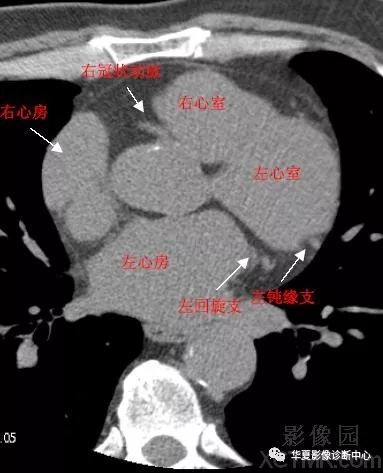

心脏ct横断面解剖

心脏ct横断面解剖,心脏ct横断面解剖图

影像解剖心脏冠状动脉ct解剖中文详细标注图文

带你全面了解心脏冠状动脉ct解剖

心脏冠状动脉ct解剖中文详细标注(图文 cardiac anatomy

主动脉根部层面ct和mri断层解剖

心脏ct横断面解剖图

心脏ct解剖

心脏ct解剖图